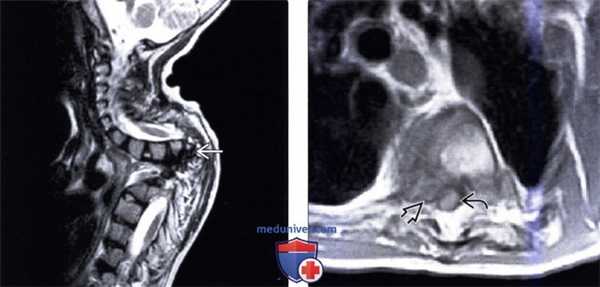

(Слева) Трехмерная КТ-реконструкция: несбалансированный правосторонний L3 полу позвонок, являющийся в данном случае причиной правосторонней сколиотической деформации. Корень дуги и задние элементы L3 позвонка слева в данном случае представлены рудиментарными фрагментами.

(Справа) На фронтальном Т2-ВИ грудопоясничного отдела позвоночника у пациента со сколиозом обнаружен сегментированный несбалансированный правосторонний L3 полупозвонок. Такая односторонняя несбалансированная конфигурация у данного пациента стала причиной врожденной сколиотической деформации.

(Слева) На сагиттальной МРТ (Т2 ВИ) отсутствует правая ножка С7, сформировано патологическое широкое отверстие, содержащее корешки С7 и С8.

(Справа) На аксиальной МРТ (Т2 ВИ FS) определяется отсутствие правой ножки С7 с наличием широкого межпозвонкового отверстия, в котором находятся корешки С7 и С8.